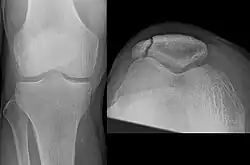

Osteochondral fracture of patella

Vertical patella fracture